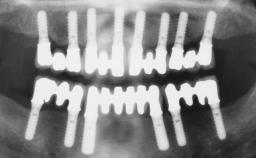

Immediate Loading of Four Implants in the Mandible and Final Restoration with a Full-Arch Metal Framework FDP

Pedro Tortamano, Luiz Otávio Alves Camargo

A fully edentulous 65-year-old woman was referred to our clinic for esthetic and functional dental rehabilitation. The patient presented with inadequate complete maxillary and mandibular prostheses, insufficient vertical dimension, and extensive tooth wear. The clinical examination and anamnesis showed no local or systemic contraindications, no signs or symptoms of bruxism, and an absence of smoking habits. The treatment proposed was implant placement in the mandibular interforaminal area and immediate loading with a fixed definitive prosthesis. A removable mucosa-supported complete prosthesis was indicated for the upper jaw, since its bone structure offered satisfactory retention and the financial condition of the patient disfavored a full-mouth implant-supported rehabilitation.

# of Implants 4

Type of Implants One-Piece

Defining Characteristics Fully edentulous lower jaw to be rehabilitated with two or more implants

Modality 3 or 4 interforaminal implants

Defining Characteristics Fully edentulous lower jaw to be rehabilitated with an implant-borne fixed dental prosthesis

Loading Protocol Immediate

Retention Screw-retained, with 4 or more splinted implants Screw-retained, with 4 or more splinted implants